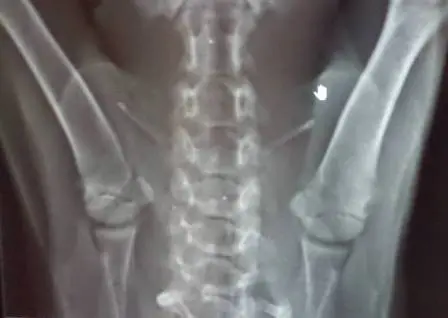

O bichinho foi recolhido e levado para o Centro de Referência Veterinária (CRV), na Barra da Tijuca, Zona Oeste. Exames de raios X constataram que uma lesão no nervo cervical fez com que o animal perdesse os movimentos nas patas da frente.

A radiografia que mostra a lesão na cervical. (Foto: Arquivo pessoal)